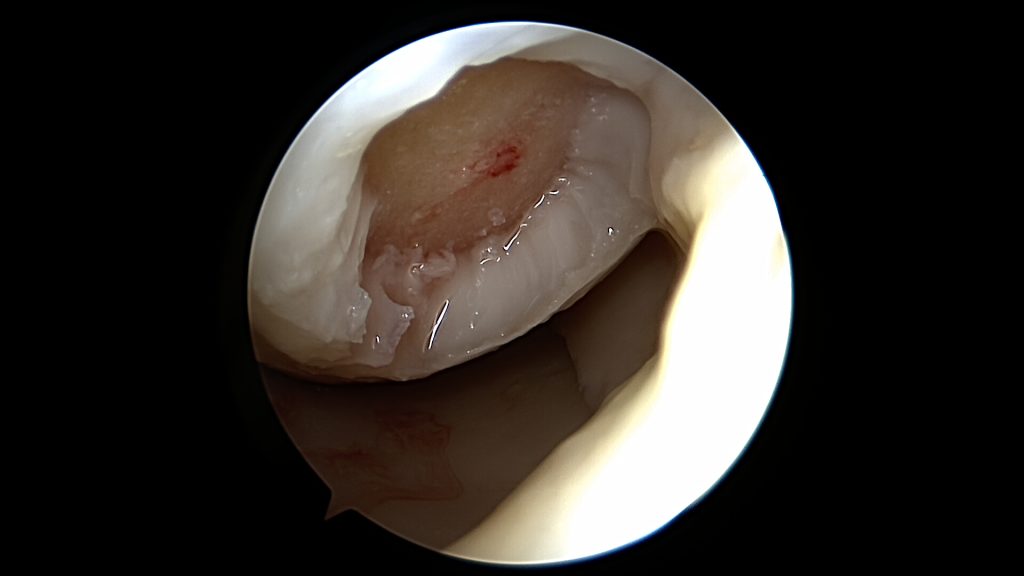

Do uszkodzenia chrząstki stawowej dochodzi w momencie urazu kolana, powtarzających się obciążeń czy chorób jak np. reumatoidalne zapalenie stawów. Może też być ona uszkadzana wtórnie poprzez inne elementy stawu (np.: uszkodzona łąkotka, ciało wolne). Wyróżniamy cztery stopnie jej uszkodzenia:

Uszkodzenia trzeciego i czwartego stopnia najczęściej wymagają leczenia operacyjnego. Same w sobie dają większe dolegliwości. Pozostawienie ich bez zaopatrzenia chirurgicznego może skończyć postępem oraz powiększaniem się uszkodzeń zarówno samej chrząstki jak i innych struktur w stawie. Leczenie zachowawcze w tych przypadkach nie przynosi oczekiwanych rezultatów.